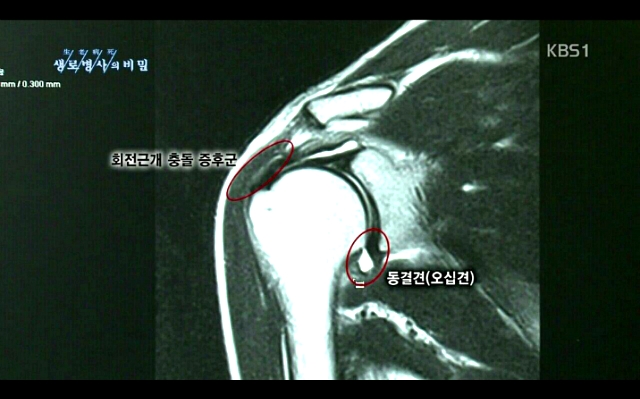

생로병사의 비밀 보다가 캡처 했습니다.

왜 진단이 중요하냐면 오십견은 고유한 진행과정을 가지고 있기 때문에 하루이틀 치료받아서는 호전이 전혀없기 때문이죠.  많일 한달만에 오십견이 낫거나 좋아졌다면 이는 오십견이 아니거나 1년이 넘어간 오십견일 수 있습니다.

오십견은 1년에서 2년정도 지나면 자연히 낫는 질환이기 때문이죠 하지만 이말도 현재는 잘 못되어있습니다.

오십견을 적절히 치료하지 않는다면 4-7년도 가고 가동범위의 제한이 남는 휴유증을 유발시킬 수도 있기 때문에 오십견은 적절한 운동치료와 컨디션 조절이 필 수 입니다. 오십견은 또한 면역질환이기도 하기 때문이죠..!!